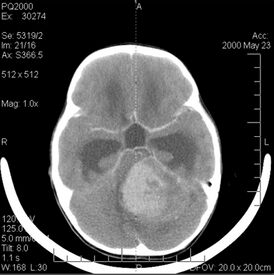

Компьютерная томография головы больного с медуллобластомой

КТ головы девочки 6 лет с медуллобластомой в области задней черепной ямки

Компьютерная томография

В типичных случаях на КТ медуллобластомы определяются как объёмные образования круглой или овальной формы, которые неоднородно накапливают контрастное вещество и располагаются в проекции червя мозжечка. Данные новообразования смещают IV желудочек вентрально. Достаточно часто определяются кисты (до 65 %) и микрокальцинаты[20].